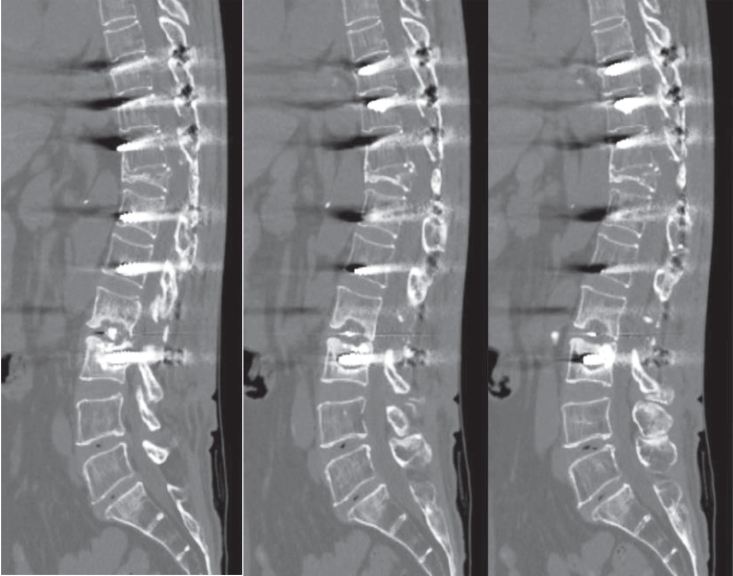

Postoperative imaging was essential for evaluating surgical outcomes. Standard radiographs and computed tomography (CT) scans were used to assess screw position and integrity. Mechanical failures—including pull-out and screw loosening—were identified by the appearance of a halo around the screw, indicating loss of fixation.10) Fig. 1 shows a typical pull-out, where the screw disengages from the vertebral body, whereas Fig. 2 demonstrates screw loosening, identified by the halo sign on CT imaging.

Fig. 1.

Postoperative radiograph demonstrating screw pull-out from the vertebral body.

Fig. 1. Postoperative radiograph demonstrating screw pull-out from the vertebral body.